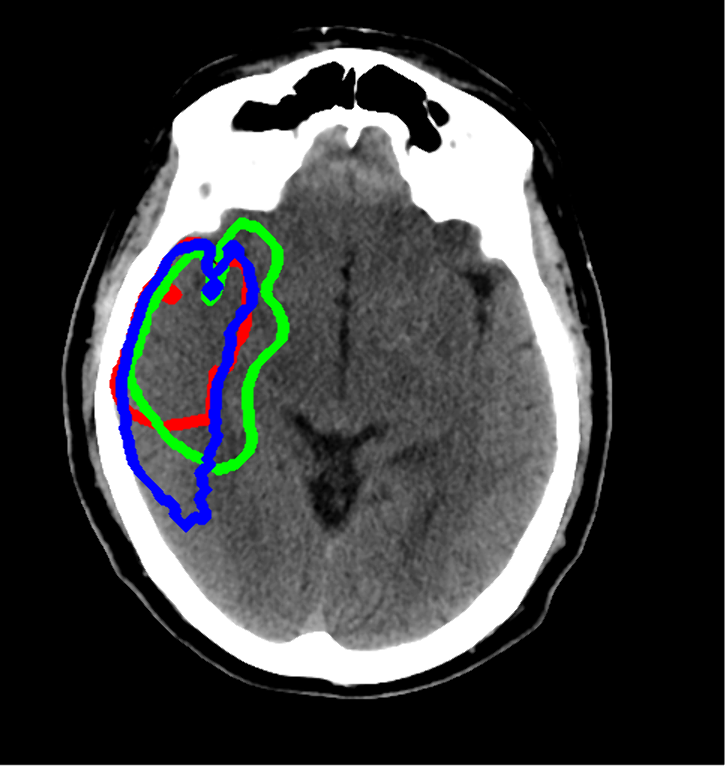

We implemented a 3D Convolutional Neural Network (CNN) based on Isensee’s nnU-Net to segment EIC in NCCT. Our dataset included 538 images labelled for EIC by expert neuro-radiologists, of which 438 were used for model development and 100 were used for testing. The interrater lesion segmentation agreement between the two experts on the test dataset was used as the benchmark against which the model’s performance was tested (Figure 1). Volumetric measurements were compared using Pearson’s r. Spatial measurements were evaluated using Dice Similarity Coefficient (DSC) on lesion-positive only cases as DSC is not well defined on lesion-negative cases.

Figure 1: An example showing the three segmentations, namely, Reader-1, Reader-2, and nnU-Net segmentations shown in red, green, and blue, respectively.